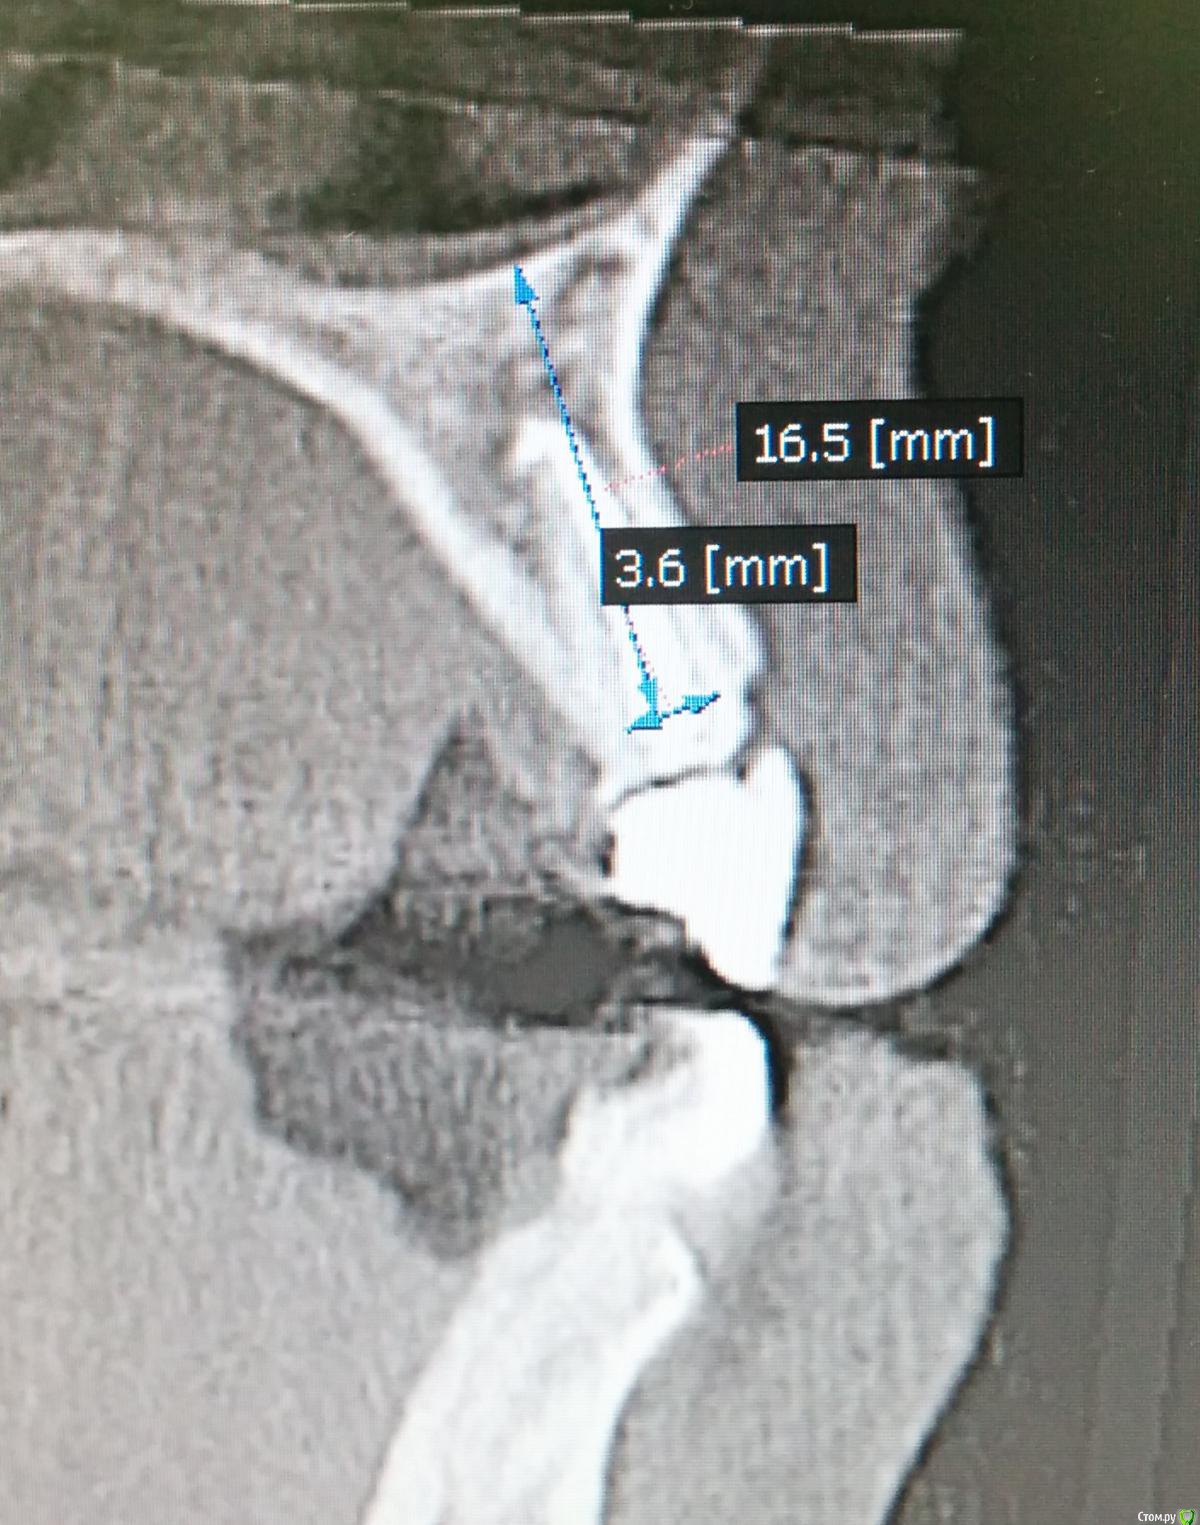

MenshikovDV Опубликовано 2 апреля, 2015 Поделиться Опубликовано 2 апреля, 2015 (изменено) Зуб 1.2 отлом коронковой части зуба, на период ожидания приема у хирурга и ортопеда (2 дня) приклеен к соседям. Вся процедура в одно посещение. Где-то часа два. Я ортопед, хирургия не моя, фото мои Изменено 2 апреля, 2015 пользователем MenshikovDV 19 Ссылка на комментарий